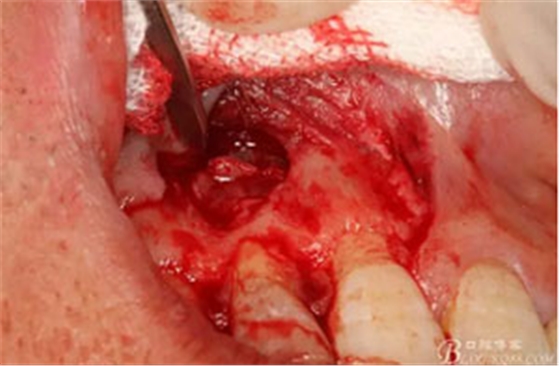

圖10。用骨膜剝離器沿著骨壁、緩慢逐漸剝離囊壁。

圖11。21囊壁被完整的剝離開來。